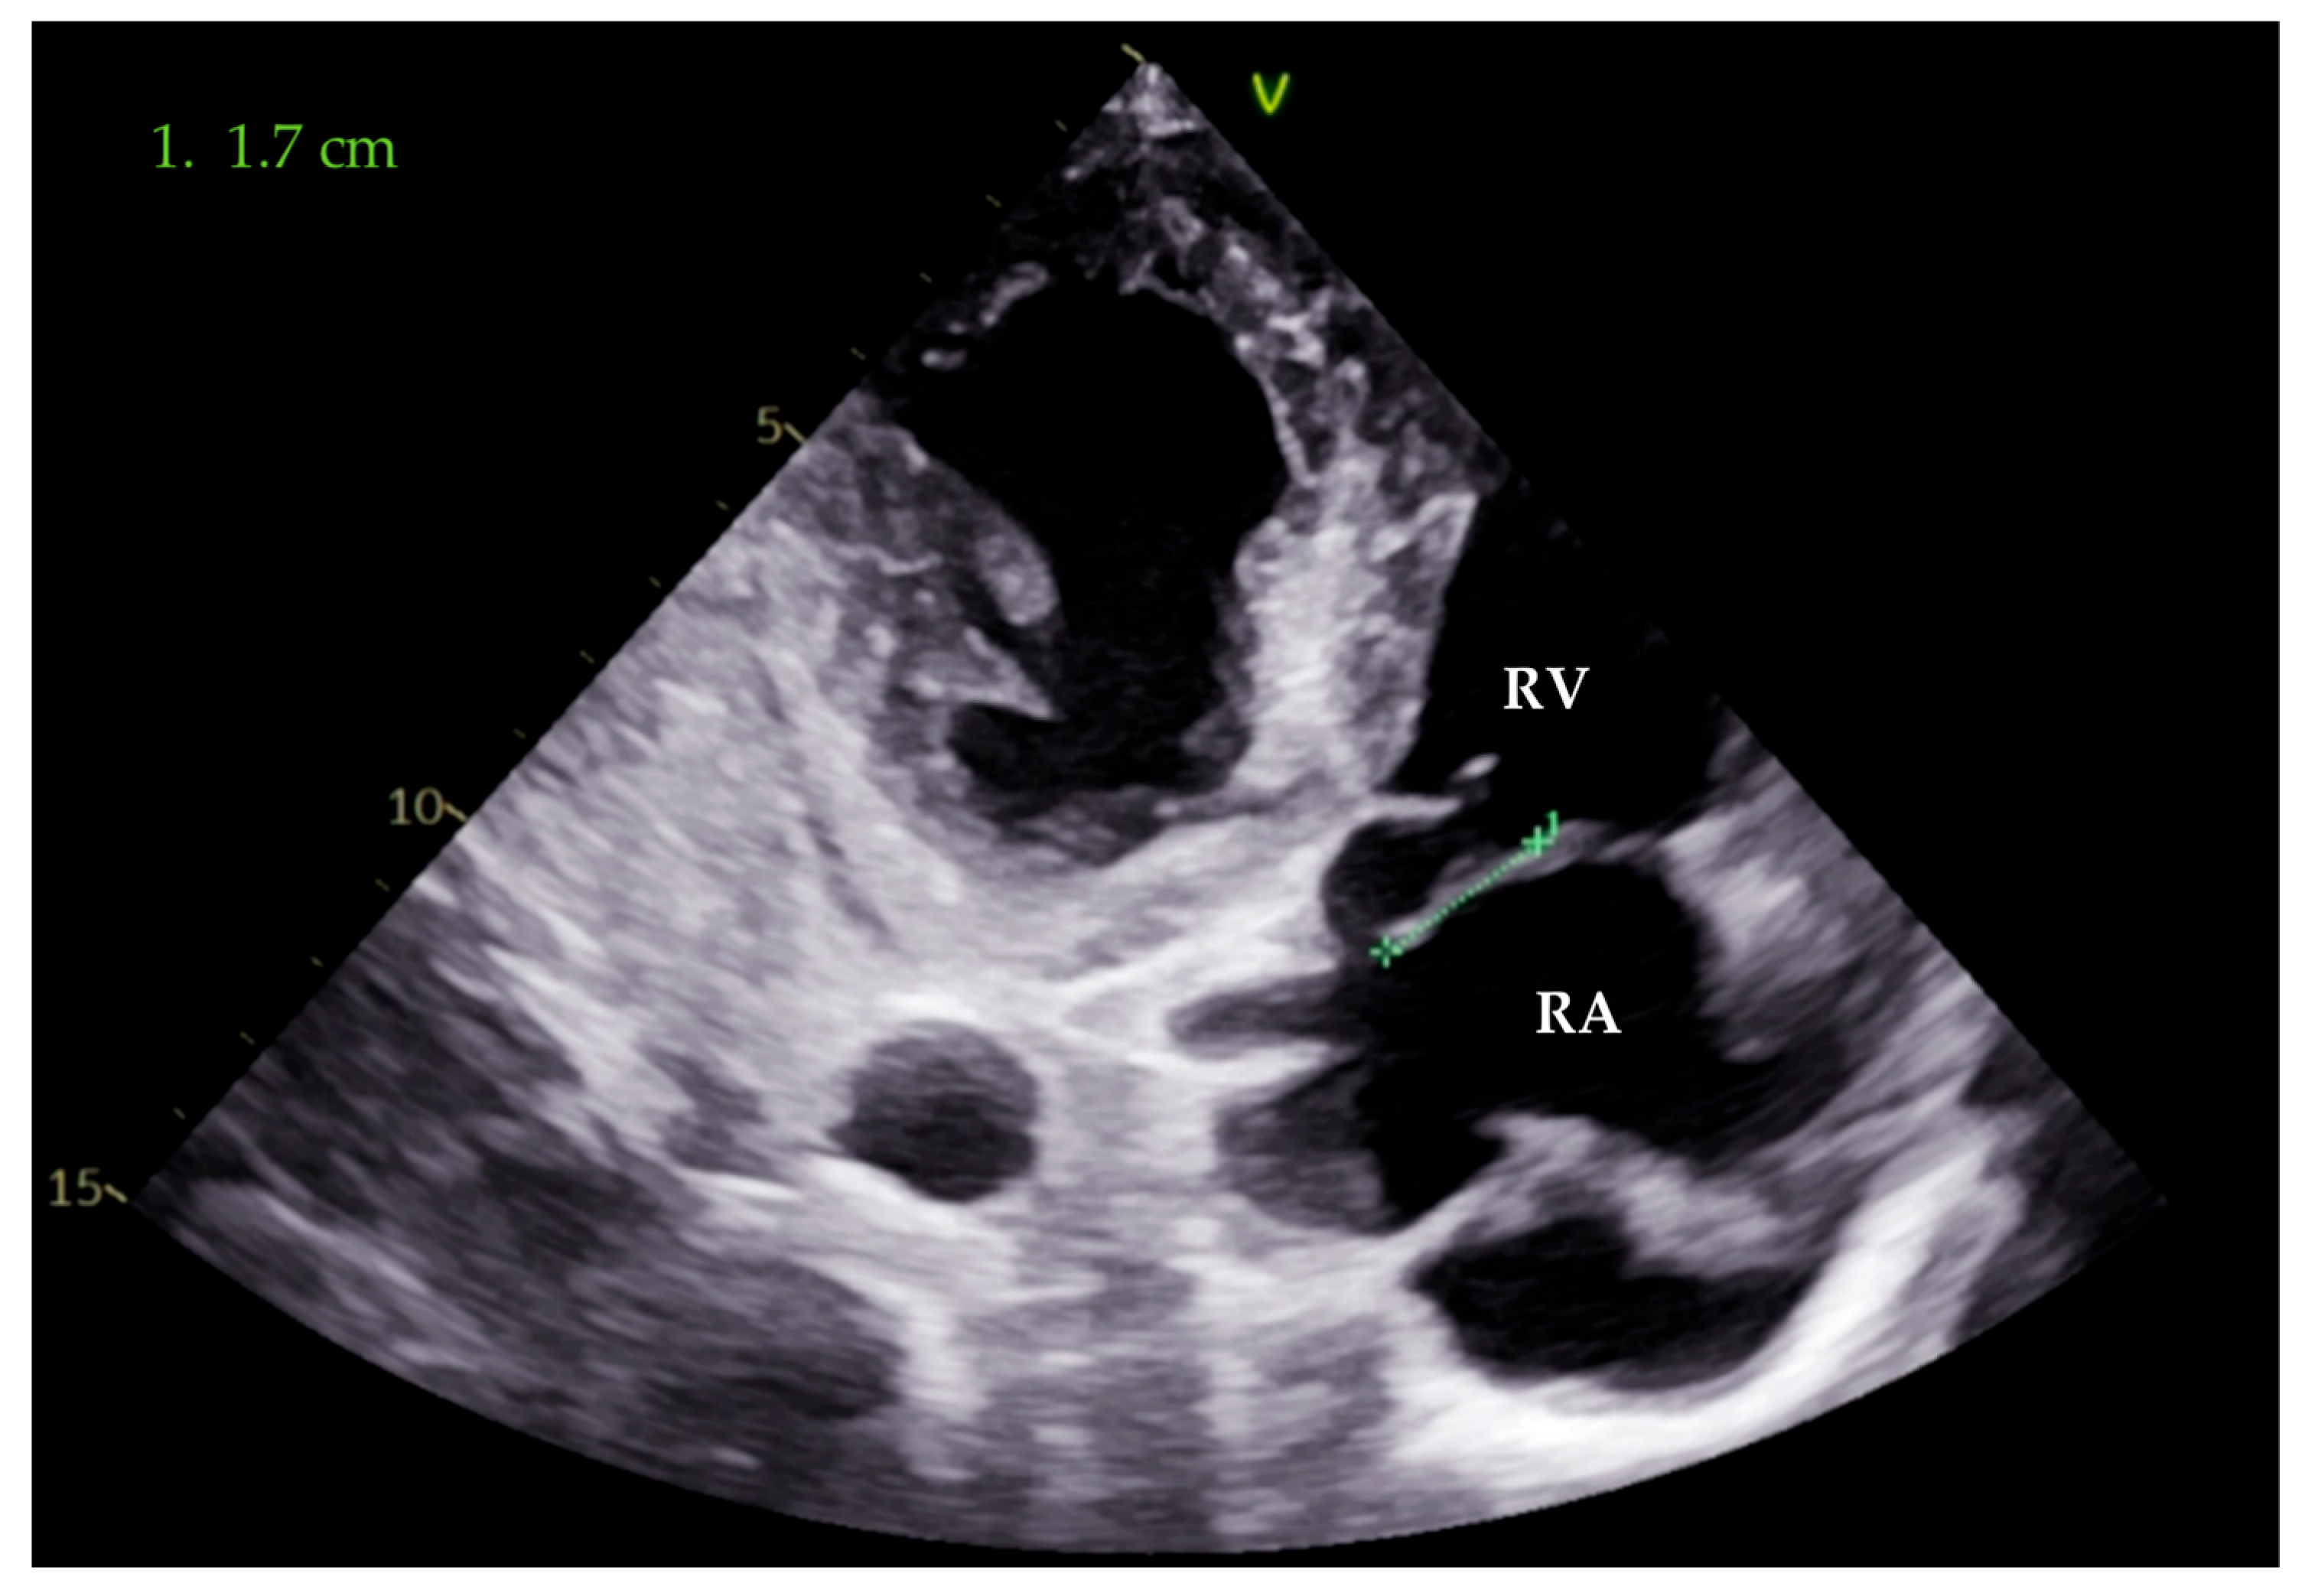

2. Case Presentation